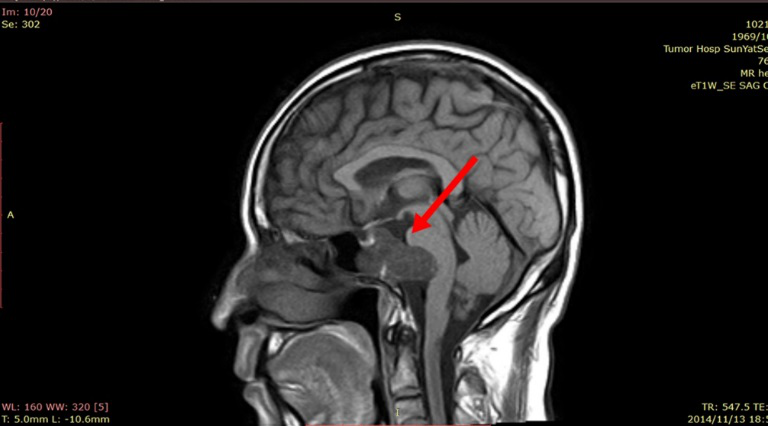

↓2013年12月7日MRI

2014年08月13日、2014年11月13日、2015年02月06日、2015年08月14日四次复查MR 瘤体均未见扩张迹象。2015年8月建议继续每年进行一次MRI检查。

2014年11月13日